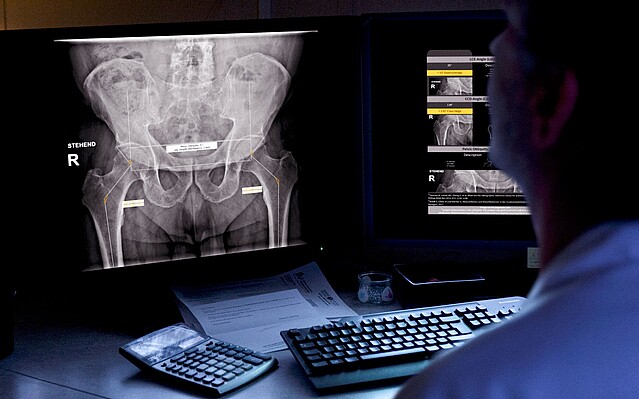

Die zugrunde liegende Technologie der Software von ImageBiopsy Lab basiert auf maschinellem Lernen – also darauf, dass Computer aus Beispielen vorheriger Fälle lernen. Tausende Röntgenbilder, von Ärzt*innen manuell markiert, dienen als Trainingsdaten: Sie zeigen der Software, wo etwa Gelenkspalten, Knochenwinkel oder Brüche liegen. Das System lernt, ähnliche Strukturen in neuen Bildern automatisch zu erkennen und zu vermessen. Die Lösungen von ImageBiopsy Lab erkennen in Sekundenschnelle relevante Strukturen, messen definierte Parameter und erzeugen einen strukturierten Analysebericht – standardisiert und reproduzierbar. So entsteht eine belastbare Grundlage für Diagnostik, Verlaufskontrolle und Therapieentscheidungen.

Heute hat ImageBiopsy Lab sieben zertifizierte Module ((MDR/TÜV SÜD, teil auch von der US-FDA) auf dem Markt. Sie decken zentrale anatomische Regionen wie Knie, Hüfte, Wirbelsäule oder Fuß ab und liefern standardisierte Analyseberichte, die in radiologischen und orthopädischen Praxen in Deutschland, Österreich und der Schweiz eingesetzt werden. Installiert „on-premise“ laufen sie im Hintergrund und liefern Zusatzinformationen direkt zum Bild.